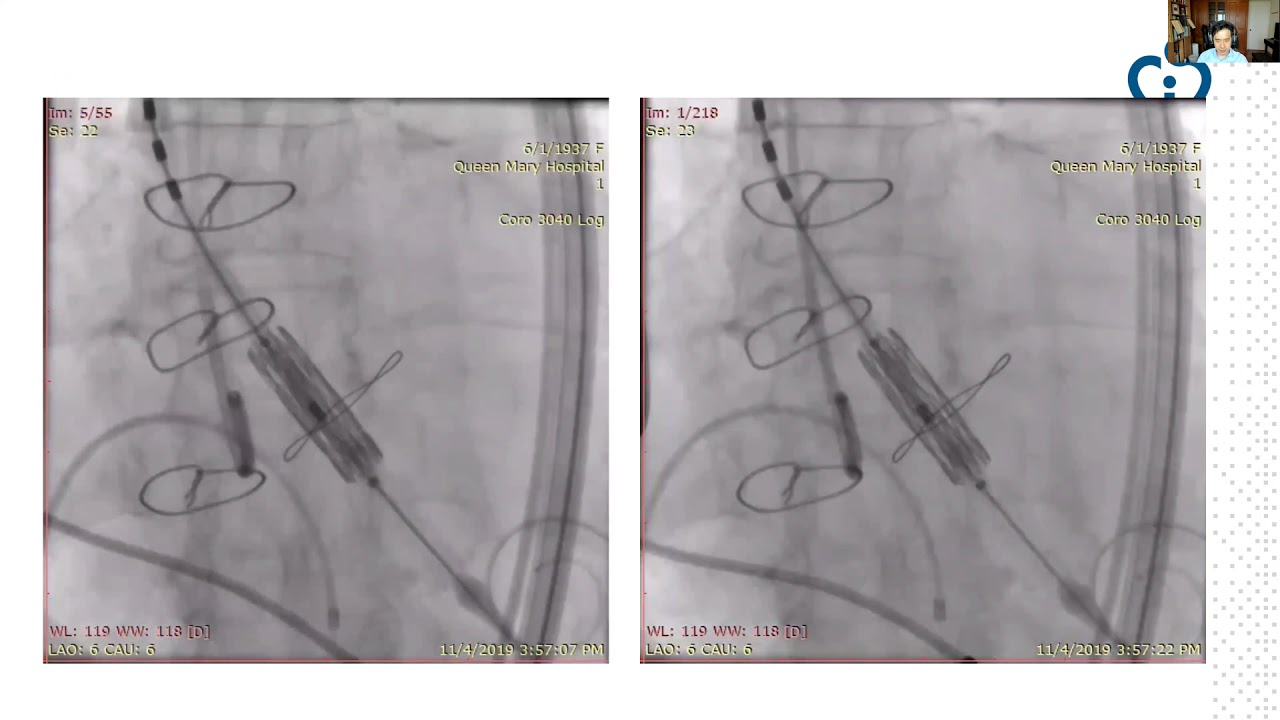

Valve-in-valve transcatheter aortic valve implantation with modification of Soprano bioprosthetic valve, with rupture of dilatation balloon during valve fracture

By: Jonathan Fang, Queen Mary Hospital, Hong Kong

An Unintended Fall

By: Un Ka Chun, Queen Mary Hospital, Hong Kong